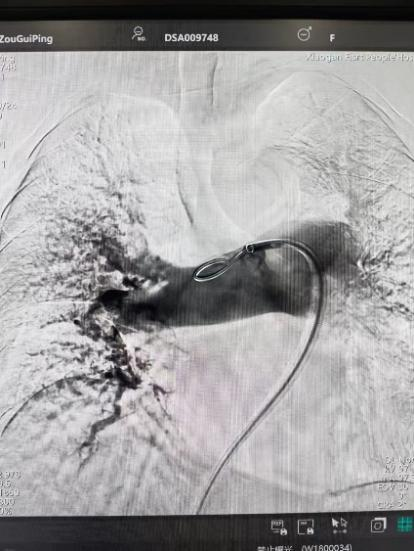

術(shù)前

手術(shù)在局部麻醉下進行,團隊通過股靜脈穿刺,將專用抽栓導(dǎo)管精準送達肺動脈栓塞部位,利用負壓抽吸技術(shù)成功清除大量血栓;隨后,在血栓局部精準灌注溶栓藥物,進一步溶解殘余血栓,恢復(fù)肺部血流灌注;同時,為防止下肢深靜脈血栓再次脫落引發(fā)肺栓塞,團隊為患者置入下腔靜脈濾器,整個手術(shù)歷時約1小時。術(shù)后,鄒婆婆呼吸困難癥狀即刻得到緩解,血氧飽和度顯著提升,右心負荷明顯減輕,目前身體狀況正在逐步恢復(fù)中。